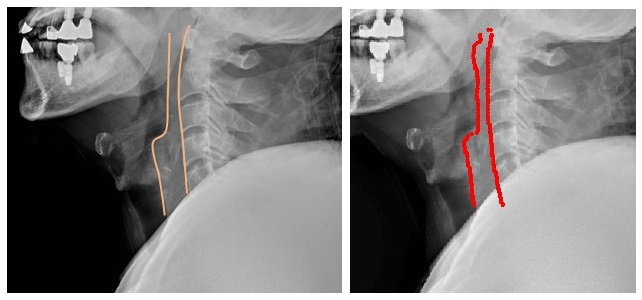

½ÇÁ¦ Ä¡°ú º¸Ã¶Ä¡·á¸¦ ¹ÞÀº ¿Ü»óȯÀÚÀÇ °æÃß X-ray ¿µ»óÀ» ¿µ»óÀÇÇаú Àǻ簡 ÆÇµ¶(»çÁø ÁÂÃø)ÇÑ °á°ú¿Í AI°¡ ÆÇµ¶(»çÁø ¿ìÃø)ÇÑ °á°ú¸¦ ºñ±³ÇßÀ» ¶§ Å« Â÷À̰¡ ¾ø¾ú´Ù.

¿¢½º·¹À̸¦ ÆÇµ¶ÇÒ ¶§ ôÃß ¾Õ °ø°£À» º¸±â À§ÇØ Ã´Ãß ¾Õ °ø°£¼±À» ±×¸®°Ô µÇ´Âµ¥, AI¿ª½Ã Àǻ簡 ±×¸° °ø°£¼±°ú °°Àº ¸ð¾çÀ» ±×·È´Ù.